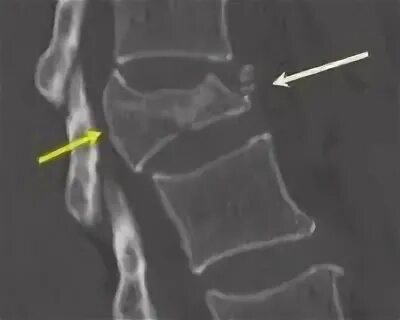

Последствия компрессионного перелома у детей